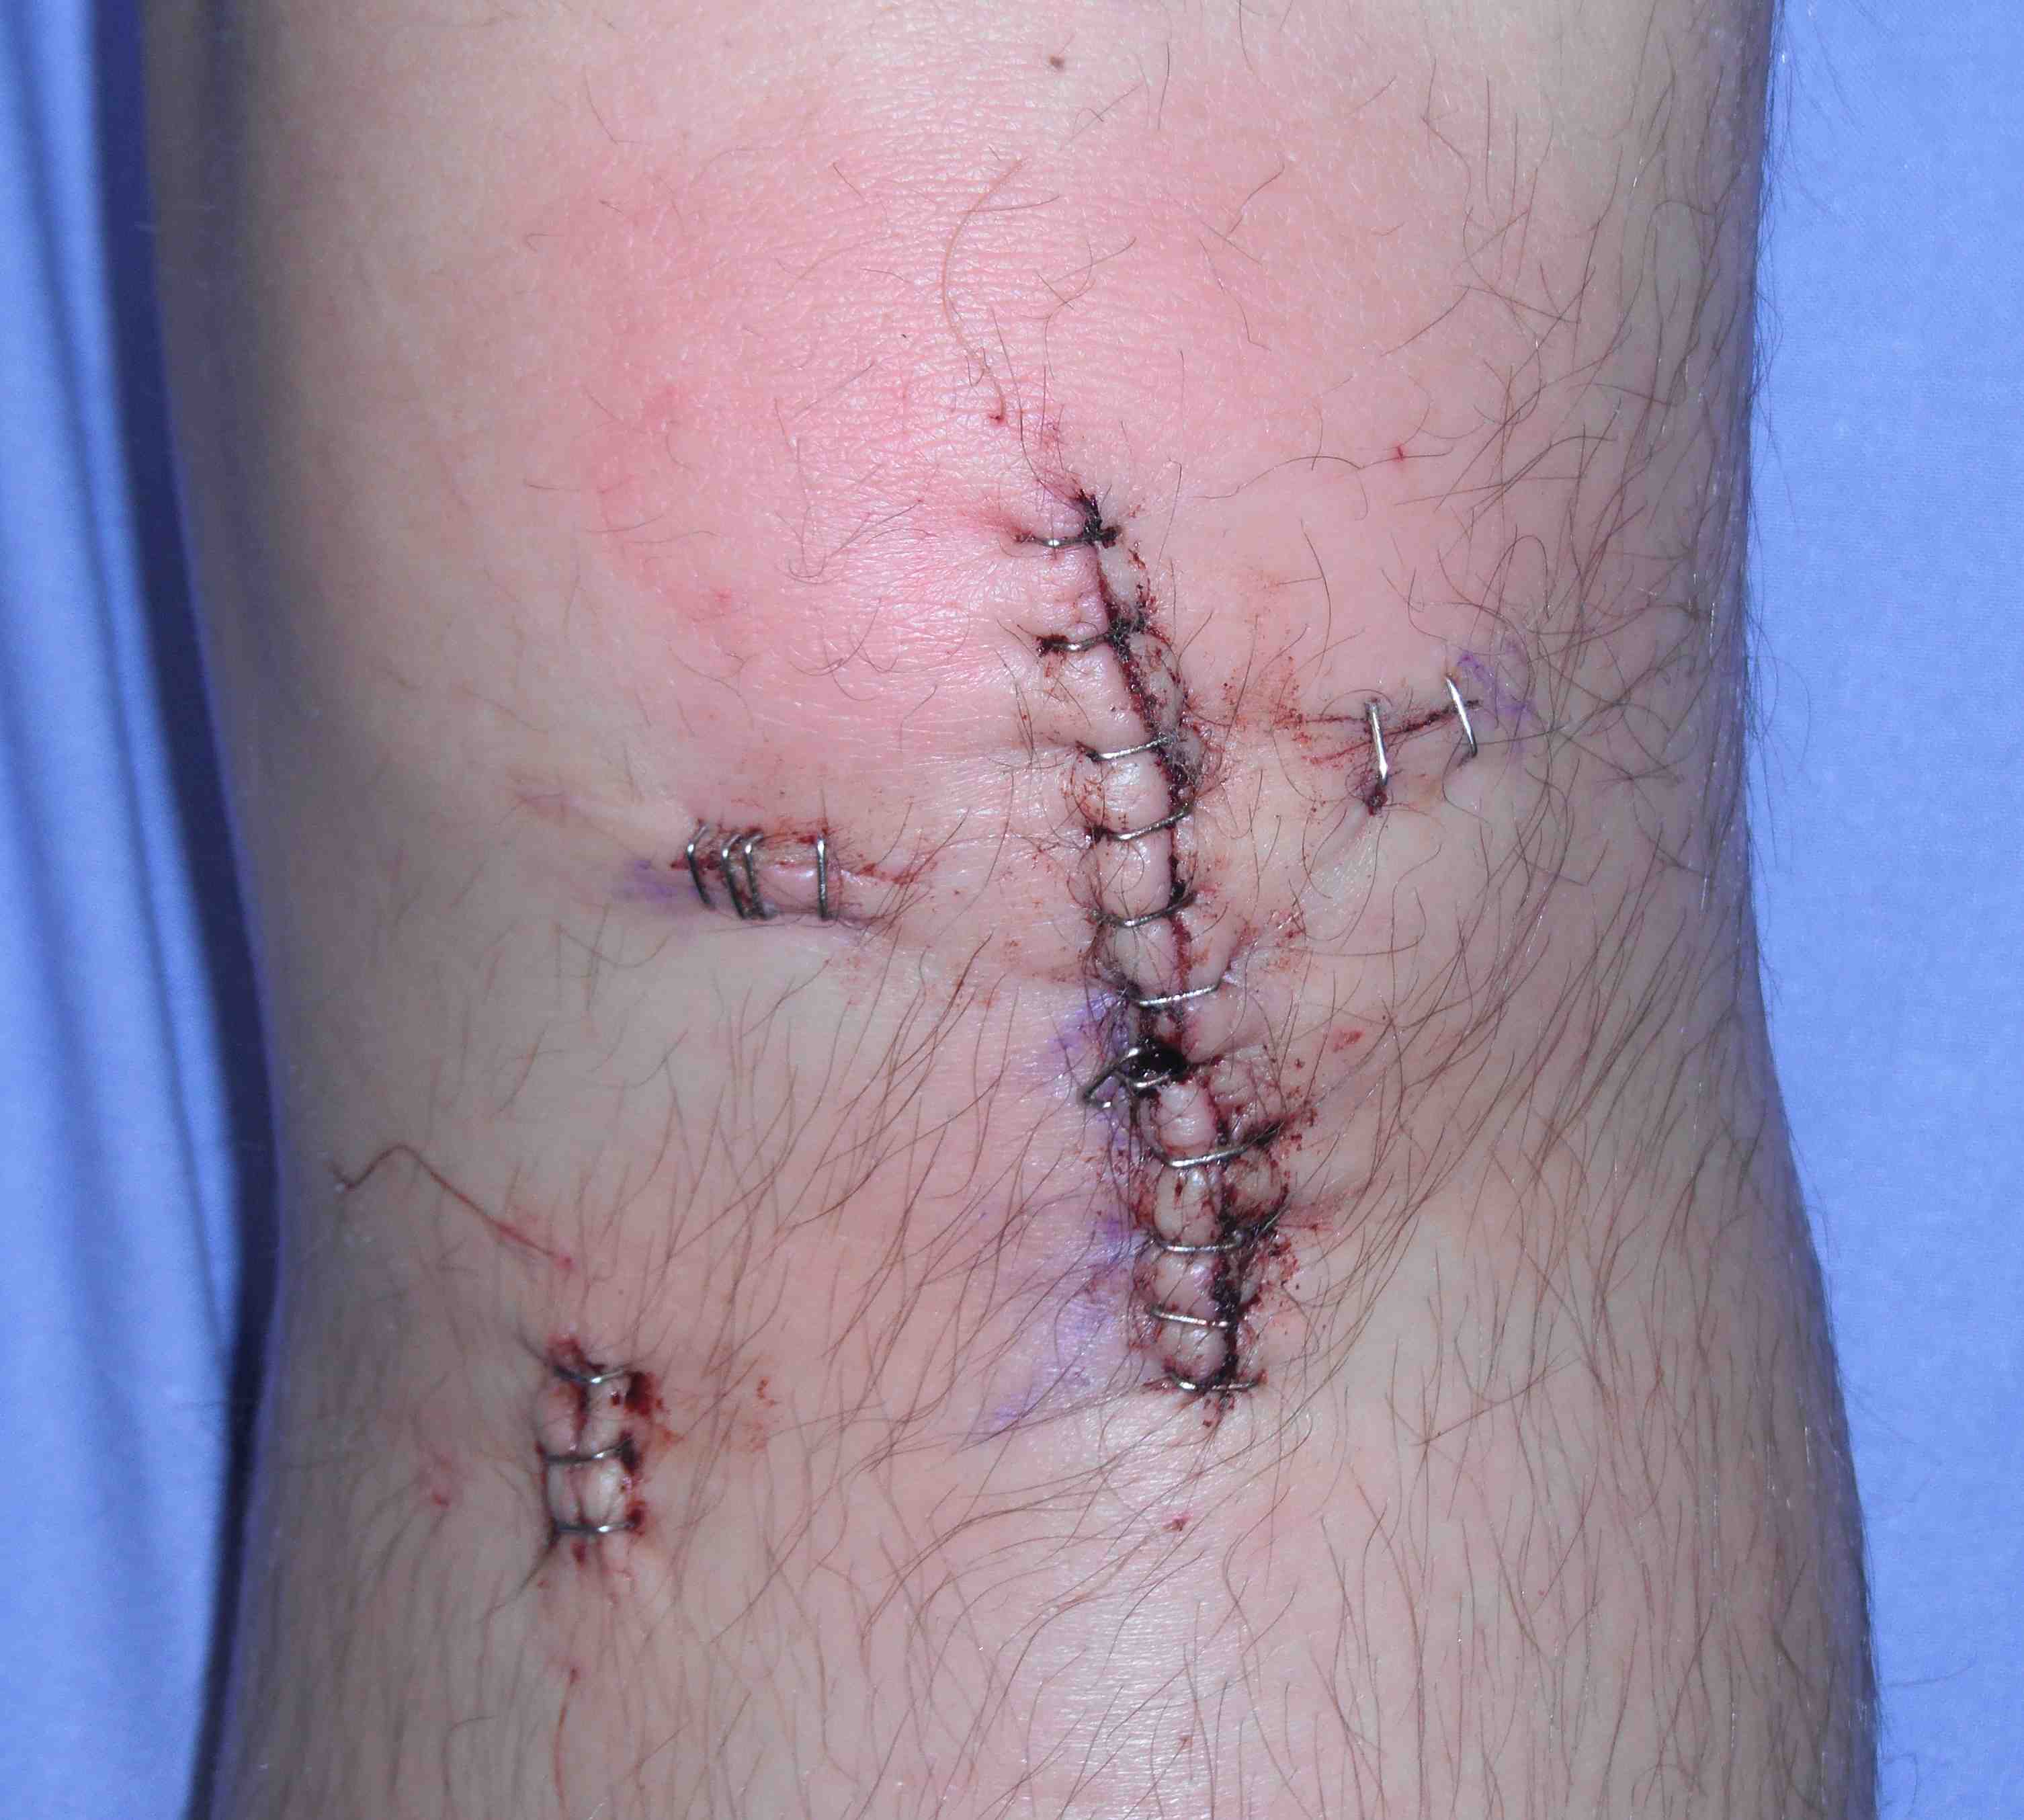

Tunnel Placement

2. X-ray assessment

3. Incorrect tunnel positions

Tibial Tunnel

A. Anterior tibial tunnel

- impingement / limits extension / cyclops lesion